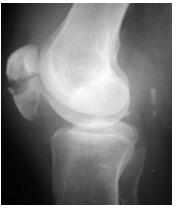

25 某 65 歲女性病患,因在浴室跌倒,主訴右膝疼痛,X 射線檢查如附圖所示。經手法整復後,下列固 定包紮的正確順序為何?

①紗布固定 ②外敷如意金黃散 ③固定抱膝 ④固定夾板 (A)③②④① (B)③②①④ (C)②③④① (D)②③①④

26 某 16 歲男性患者,某日因從事直排輪極限運動自斜板上跌下,著地時左臂撐地,旋即發生劇烈疼痛。 經送醫檢查發現其 X 光片如圖所示,則其骨折之類型於分類上應屬下列何者?

(A)骨骺分離 (B)嵌插骨折 (C)裂縫骨折 (D)青枝骨折